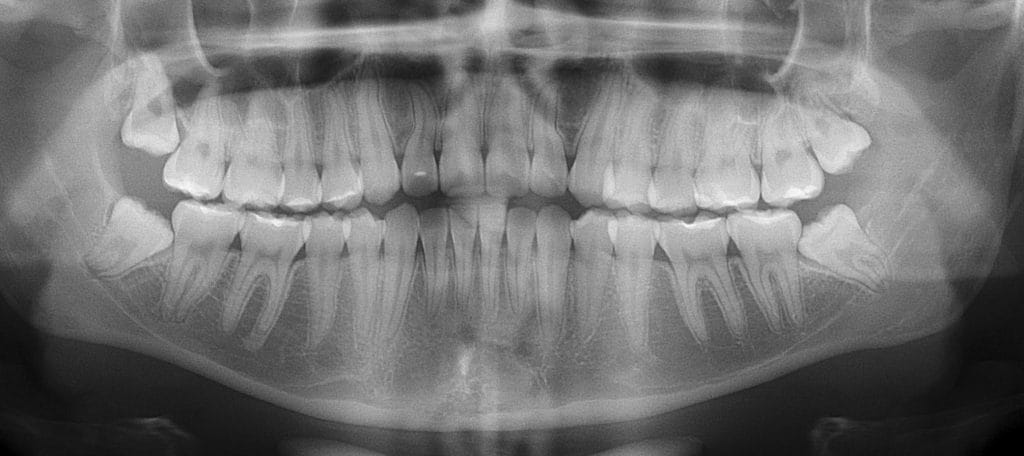

A extração do dente siso, também conhecido como terceiro molar, é um dos procedimentos odontológicos mais comuns realizados em todo o mundo.

Na Odonto Gama, oferecemos serviços especializados em Cirurgia Bucomaxilofacial para a remoção de dentes do siso em casos complexos, como dentes inclusos, impactados ou próximos de estruturas sensíveis como nervos e seios maxilares.

Na Odonto Gama, realizamos a extração de siso com máxima segurança, mesmo em casos complexos. Se o seu dente do siso está incluso, impactado, deitado, dentro do osso ou próximo ao nervo, a cirurgia exige um especialista qualificado.

Os dentes do siso podem nascer de forma irregular, causando dor, inflamação e dificuldades na higienização.